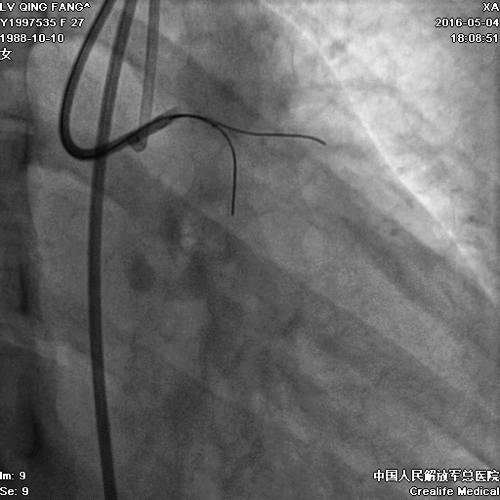

PCI